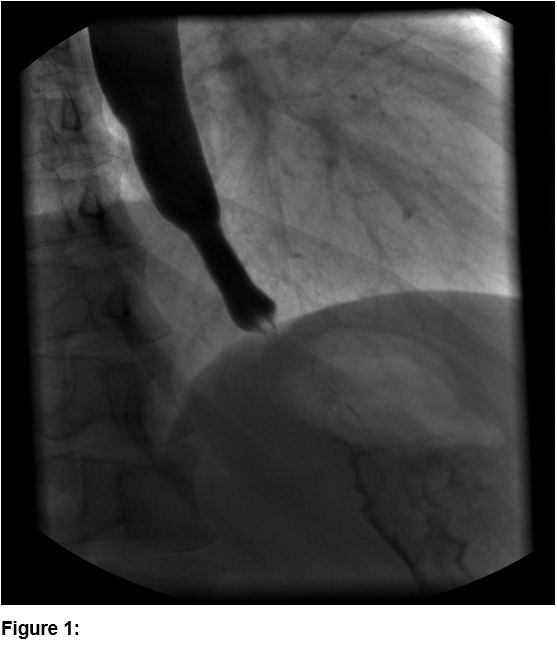

The clinical examination showed a patient in good general health condition with a BMI of 20 (kg/m2). The inspection of the throat and the oral cavity has not shown any pathologic findings. The most frequent triggers of dysphagia in the age group of 20-49 years [2,3] are due to mechanical obstruction (median neck cyst, nasopharyngeal carcinoma, disorders of the thyroid gland, etc.), autoimmune/inflammatory diseases (eosinophilic esophagitis, inflammatory myopathy, Sjögren’s syndrome, throat infection, etc.), esophageal dysmotility (achalasia, nutcracker esophagus, multiple sclerosis, etc.) and others (gastro esophageal reflux, anxiety disorder, heterotopic gastric mucosa, etc.).The first diagnostic procedure performed was an esophagogastroduodenoscopy with no major pathological findings, except for candida infection. The patient then proceeded to an esophageal passage with a barium swallow that showed an enlargement of the distal esophagus up to 3 cm (Figure 1). For various reasons no further diagnostic steps were performed with the diagnosis being made that this was psycho-functional. As the dysphagia was deteriorating, the patient attended our clinic to get an ultrasound examination of her neck which showed an impressive dilatation in the left lower neck area during the swallowing act, consistent with a dilatation of the lower esophagus (Figure 2, video-clip). This finding was confirmed by the subsequent esophageal manometry that was consistent with a congenital achalasia of type 2 according to the Chicago classification (figure 3).

Figure 2: Ultrasound (linear 9 MHz probe): during swallowing shows a 3 cm, sickle-shaped and hyperreflective structure consistent with a dilatation of the lower esophagus.